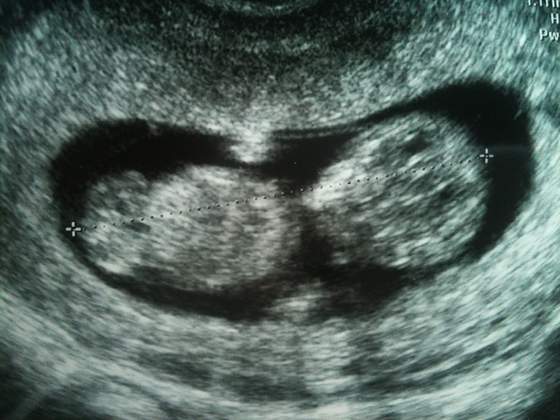

Myślę, że nie można generalizować że na NFZ to nie ma usg. Ja do tej pory byłam na trzech wizytach - na pierwszej szukaliśmy na usg kropka i był tylko pęcherzyk, więc dwa tygodnie później znowu była wizyta i usg - wtedy już było widać maleństwo i zaczątki serduszka. Tydzień temu byłam z wynikami i lekarz dał skierowania na następne badania i zrobił szybkie usg przez brzuch żeby sprawdzić akcję serca i było już pięknie je widać, wtedy też dostałam pierwszą fotkę dzidzi(wcześniejsze zostały w karcie). Do tej pory NFZ mnie rozczarował tylko tym, że nie będę mieć USG "genetycznego". Myślę, że sporo zależy od lekarza oraz sprzętu jaki ma w gabinecie